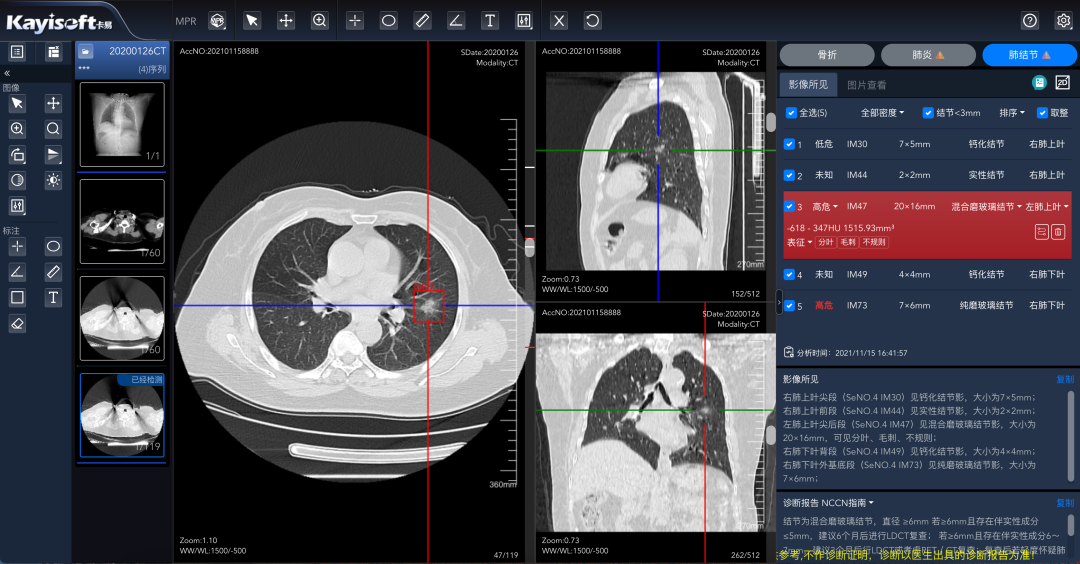

基于区域影像云的CT肺结节AI分析

这一应用通过影像数据云化管理数据统一采集,实现以数据为基础,结合 AI 分析服务,实现肺结节智能标注,降低漏诊、误诊的概率,将诊片时间从传统的5分钟,缩短到了2-3分钟。